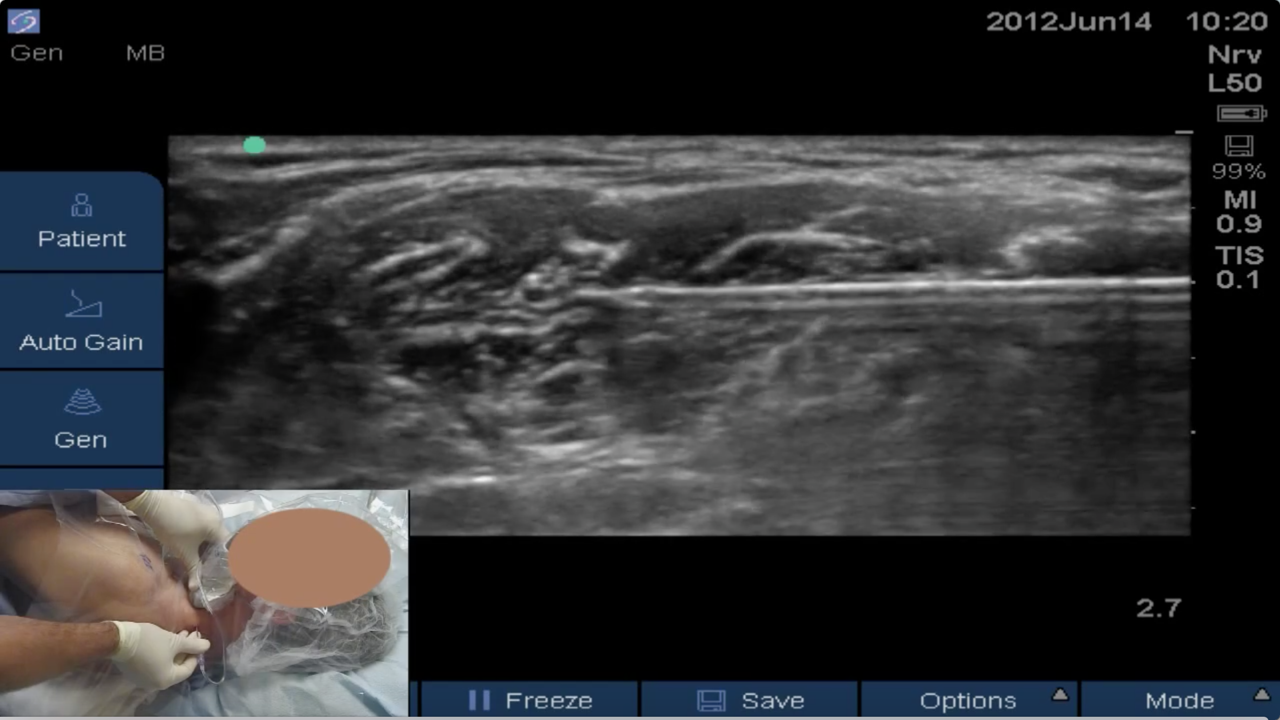

Video series of interscalene brachial plexus block and perineural catheter procedures.

BLOCKJOCKS BLOCK OF THE DAY #28: Dr. Scott Thomas, a regional anesthesia fellow at the Andrews Institute, performs a continuous interscalene catheter with ultrasound guidance (Sonosite S-Nerve) using a B-Braun Perifix styletted epidural catheter.

In this new Virtual Ultrasound Workshop video Dr. Brandon Winchester explains tips and tricks for the successful and safe placement of interscalene blocks and continuous interscalene catheters.

The BLOCKJOCKS Virtual Ultrasound Workshop comprehensively discusses and demonstrates scanning & tec...